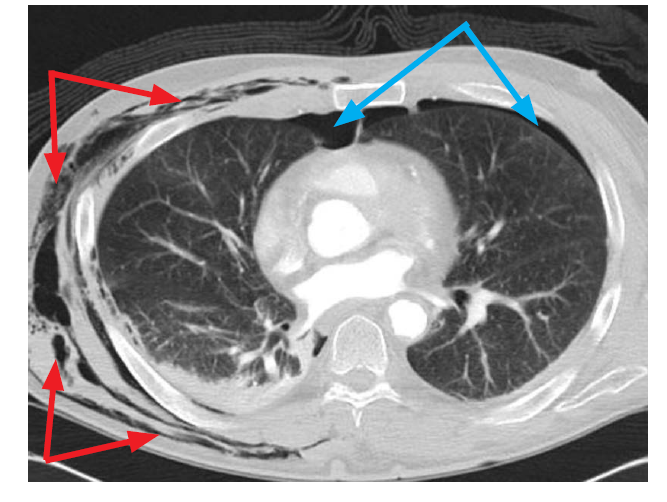

From the blue arrows, what condition is this?

Pneumothorax